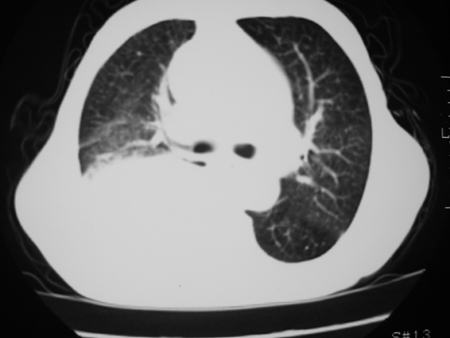

男77岁,胸痛就诊

右侧胸腔积液,部分包裹,右下肺膨胀不全,右下肺感染。

考虑右肺门占位并下叶不张 右胸包裹积液

右侧胸腔积液,部分包裹,右下肺膨胀不全

右肺中叶及下叶炎症并胸腔积液(部分包裹),建议抽液后复查ct除外占位。